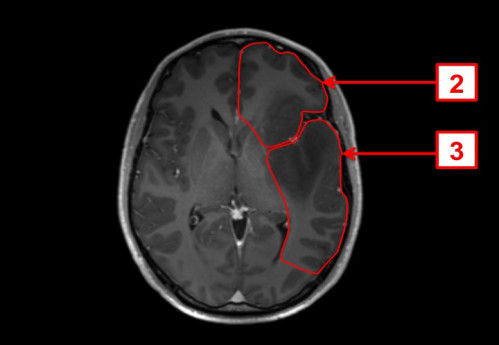

ICD: C71.9

ICD: R47.0

ICD: R51

23-jähriger Mann. Bereits seit Jahren plagen ihn Kopfschmerzen, die vor allem bei körperlicher Belastung auftreten. In den letzten Tagen fühlte er sich zunehmend unwohl, die Kopfschmerzen sind nun auch in Ruhe vorhanden.

Seit gestern Abend erbricht er sich mehrmals, und spricht, als ob er betrunken wäre.